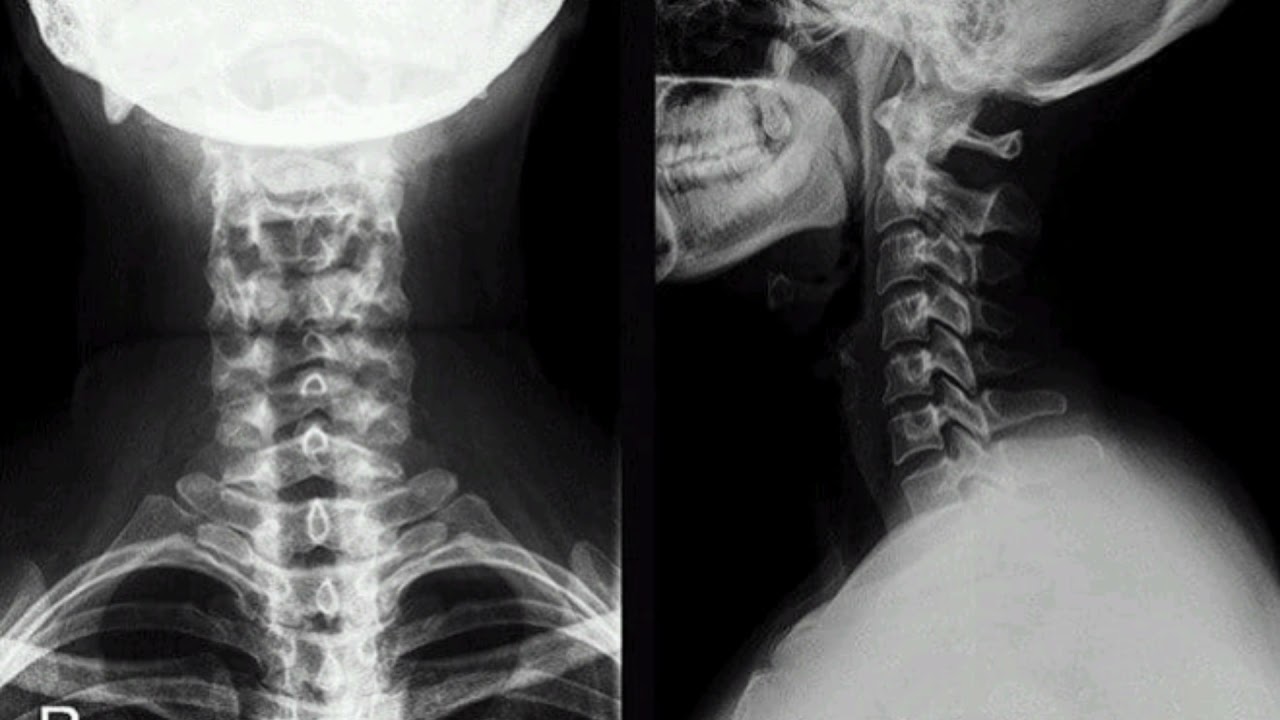

- X-rays: To visualize vertebrae and identify abnormalities

- X-rays show your vertebrae to help identify or rule out growths, injuries, and abnormalities.

Imaging techniques such as radiography, MRI or computed tomography can provide a detailed morphological picture of spinal tissues. Electromyography (EMG) may also be done to measure electrical activity and conduction from nerves to muscles.